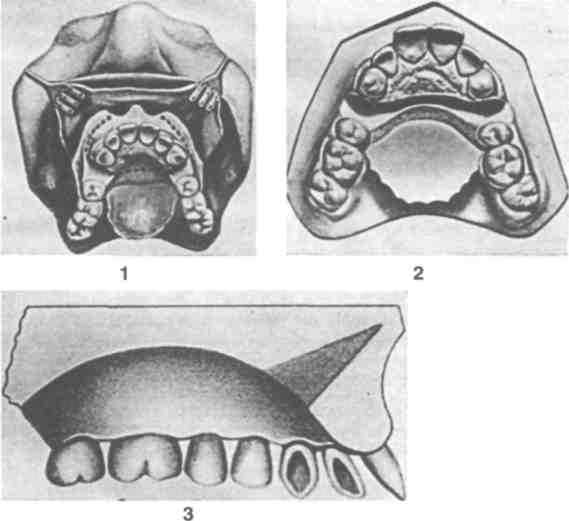

Рентгенография небного шва: Медицинские исследования и диагностика